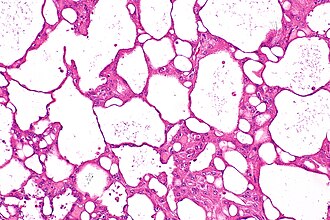

Acquired cystic disease-associated renal cell carcinoma. H&E stain. | |

| LM | sieve-like architecture (tubular structures/cribriforming), tumour cells with prominent nucleoli and eosinophilic cytoplasm, oxalate crystals - seen best in polarized light, acquired cystic disease in background, +/-papillary structures - common minor component |

- Fused tubular structures/cribriforming/sieve-like architecture.[4]

- Focal papillary architecture - common.[3]

- Tumour cells have prominent nucleoli (ISUP nucleolar grade 3) and eosinophilic cytoplasm.

- Oxalate crystals - important.

- Look somewhat like cholesterol clefts.

- Seen easily in polarized light.

- Acquired cystic disease in background - required.

- Changes of end-stage kidney (obsolete glomeruli, thyroidization, interstitial fibrosis).